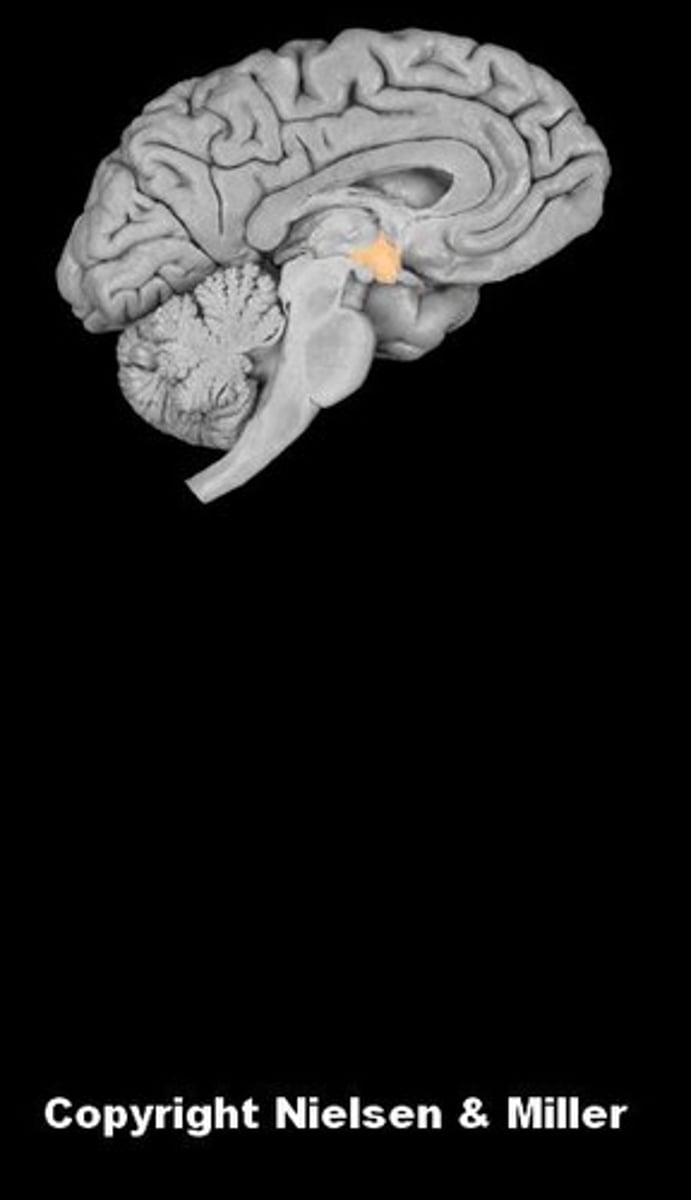

brain

cerebellum

cerebral hemispheres

cerebrum

fourth ventricle

hypothalamus

lateral ventricles

medulla oblongata

midbrain

pons